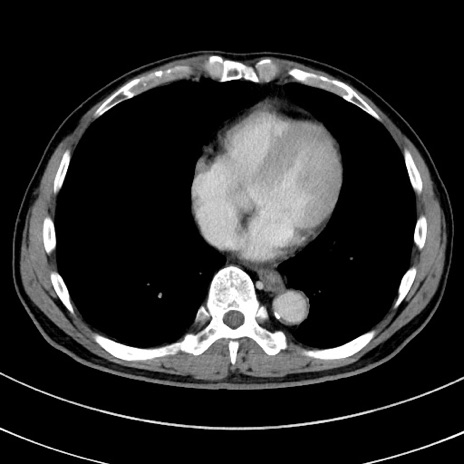

症例8(横断像)

【症例】 60歳代男性

【主訴】 黒色吐物

【現病歴】 4日前から嘔気自覚、2日前の朝食後にも嘔気あり、自分で手で嘔吐反射起こし嘔吐したところ血が混ざっていたため受診。

【既往歴】 5年前汎発性腹膜炎を伴う急性虫垂炎で手術、高血圧、前立腺肥大症、高脂血症

【身体所見】 腹部正中に手術癩痕あり 腹部平坦・軟圧痛なし膨満感あり

【データ】WBC 8400、CRP 4.54